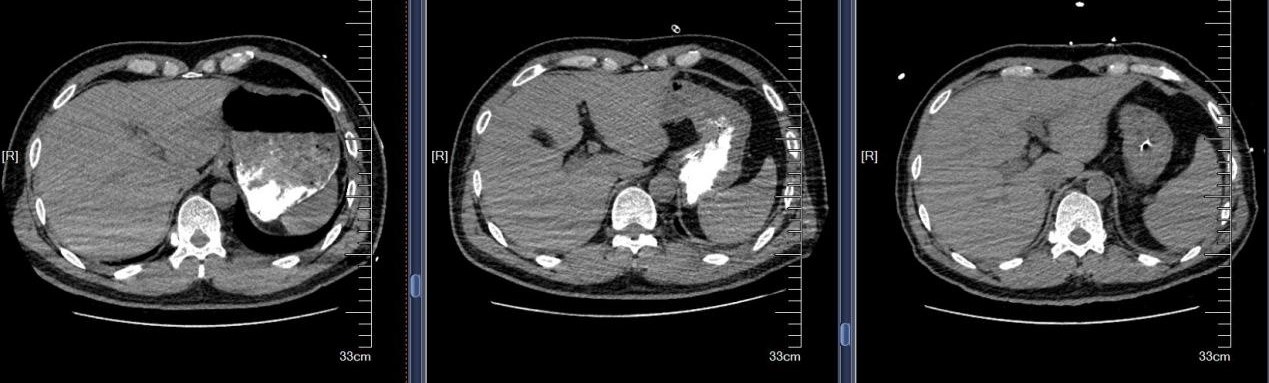

近日,苏州大学附属第四医院成功救治一例极其罕见的支气管异物危机案例。患者是一名48岁男性,因全身被水泥覆盖,伴有意识不清、呼吸困难等危急症状。紧急送医至我院后,CT检查发现其气管和双侧主支气管内充满大量高密度泥沙状异物,同时伴有多发肋骨骨折及腰椎骨折等严重外伤。面对如此复杂的病情,苏大附四院呼吸与危重症医学科蒋军红主任率领团队迅速制定了精准救治方案,成功挽救患者生命。

首次支气管镜清除手术:解决大块异物阻塞。因患者颈部有损伤,未行硬镜置入,在麻醉手术科的密切配合下,为患者经口插入8.5号气管插管,接呼吸机辅助通气,建立稳定的呼吸通道。随后,气管镜顺利进镜,发现气管及左主支气管内充满泥沙样分泌物、黄脓痰及块状异物。随后,实行精准操作:用吸引器清除泥沙样物质及黄脓痰;使用活检钳分次取出左下叶大块石状异物,并配合取石网篮清理;刷检带出细小碎石,并进行多部位生理盐水灌洗,最大限度清除可见异物。